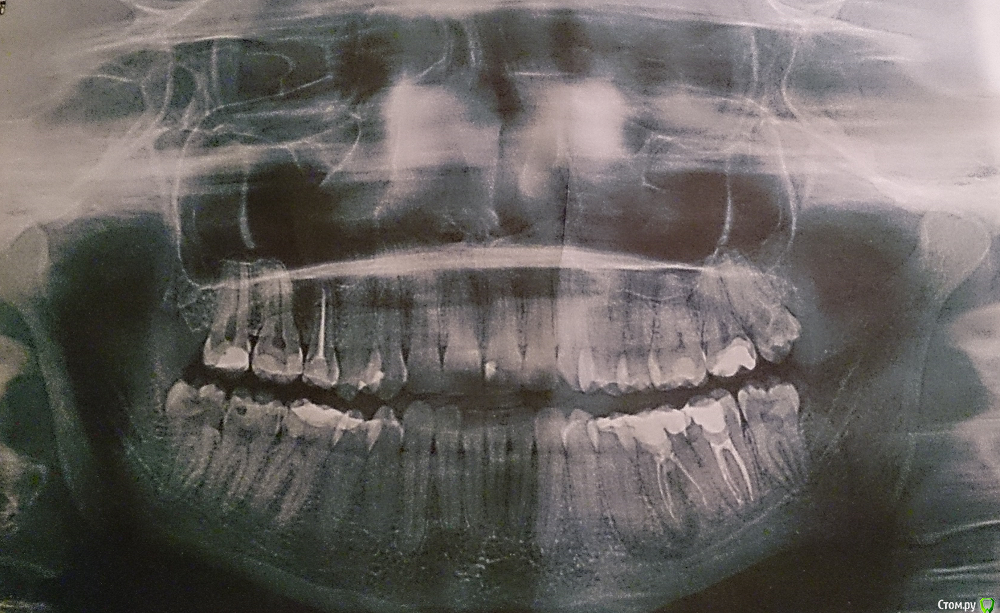

MeriRV Опубликовано 3 марта, 2016 Поделиться Опубликовано 3 марта, 2016 Добрый вечер. Подскажите, пожалуйста, какие зубы требуют лечения? Есть ли показания к удалению зубов мудрости? Ссылка на комментарий

Larnary Опубликовано 3 марта, 2016 Поделиться Опубликовано 3 марта, 2016 Добрый вечер! Удалять надо все восьмерки.В лечении нуждаются 17,15,27,36,37,47. Так же есть вопросы по 16,46.надо сделать прицельные снимки. 1 Ссылка на комментарий

MeriRV Опубликовано 3 марта, 2016 Автор Поделиться Опубликовано 3 марта, 2016 Можно ли попытаться перелечить зуб 36? Врач сказал, что он подлежит удалению. Ссылка на комментарий

DmitrySH Опубликовано 3 марта, 2016 Поделиться Опубликовано 3 марта, 2016 36. Не можно, а нужно!Только не просите это делать врача вынесшего приговор этому зубу. 4 Ссылка на комментарий